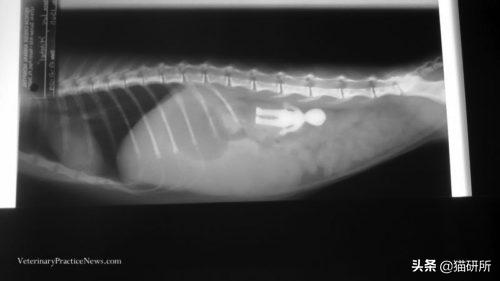

误食小玩具

有些玩具或装饰也有较小的零件,也需要家长格外留意。虽然猫咪一般不会去特意吃掉它们,但是在玩耍时容易误食。

这只小猫因严重的厌食和反复呕吐被主人带去医院检查。X射线上识别出玩偶的轮廓,手术取出后,猫咪逐渐恢复健康。

图自:veterinarypracticenews